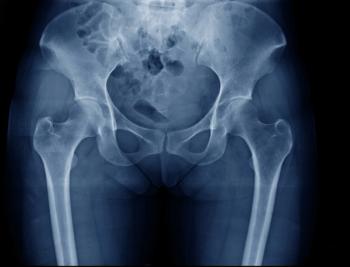

Laparoscopic management of deep endometriosis involving the sacral roots and the sciatic nerve improves patient symptoms and overall quality of life, according to a retrospective case series.